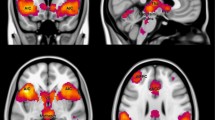

Region of interest (ROI) based results that are summarized in Fig. 4 were derived using a two-sample t-test of BOLD signal intensity differences between the aware group and unaware group for BOLD signal intensities greater in the CS+ condition than the CS− condition. Among the a priori specified ROIs, BOLD signal intensity was significantly greater in the bilateral dlPFC, right vmPFC, bilateral vlPFC, left insula, left hippocampus, and bilateral amygdala for the aware group compared with the unaware group when confronted with the same task (CS+>CS−), Markov chain Monte Carlo (MCMC) minimum cluster threshold corrected p < 0.01. Response parameters are plotted by group in Supplementary Figure 2 and indicate responses to be generally higher for the aware group compared with the unaware group. In the aware group alone, BOLD signal intensity was significant in the bilateral dlPFC, bilateral dmPFC, bilateral vmPFC, bilateral vlPFC, bilateral insula, and right amygdala, MCMC minimum cluster threshold corrected at p < 0.01 (Fig. 5). No significant differences were found in the reverse comparison (unaware > aware) or for the unaware group alone.

Two-sample t-test of intensity differences comparing aware vs. unaware for CS+>CS−. BOLD signal intensities significantly greater in the aware group compared with the unaware group for masked regions, using a two-sample t-test, are shown in the table above. Each region displayed survived the Monte-Carlo simulated cluster threshold needed to signify nonrandom activation at p threshold <0.01. Areas that showed greater intensities for the aware group were the (A) bilateral dlPFC, (B) bilateral vlPFC, (C) right vmPFC, (D) bilateral amygdala, (E) left Insula, and (F) left hippocampus. All regions displayed survived a Bonferonni correction for multiple ROIs (t ≥ 3.2272, p ≤ 0.00125) except for the left vlPFC

Random effects analysis of BOLD signal intensities in aware group for CS+>CS−. BOLD signal intensities significantly greater in the aware group alone for CS+>CS− are shown in the table above. Each region displayed survived the Monte-Carlo simulated cluster threshold needed to signify non-random activation at p threshold <0.01. Areas that showed significant intensities for the aware group were the (A) bilateral dlPFC, (B) bilateral dmPFC (left not shown), (C) bilateral vmPFC, (D) bilateral vlPFC, (E) bilateral Insula, and (F) right amygdala. All regions displayed survived a Bonferonni correction for multiple ROIs (t ≥ 3.2272, p ≤ 0.00125)